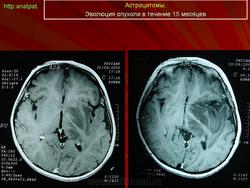

ГМ. Астроцитома. +

Астроцитома.